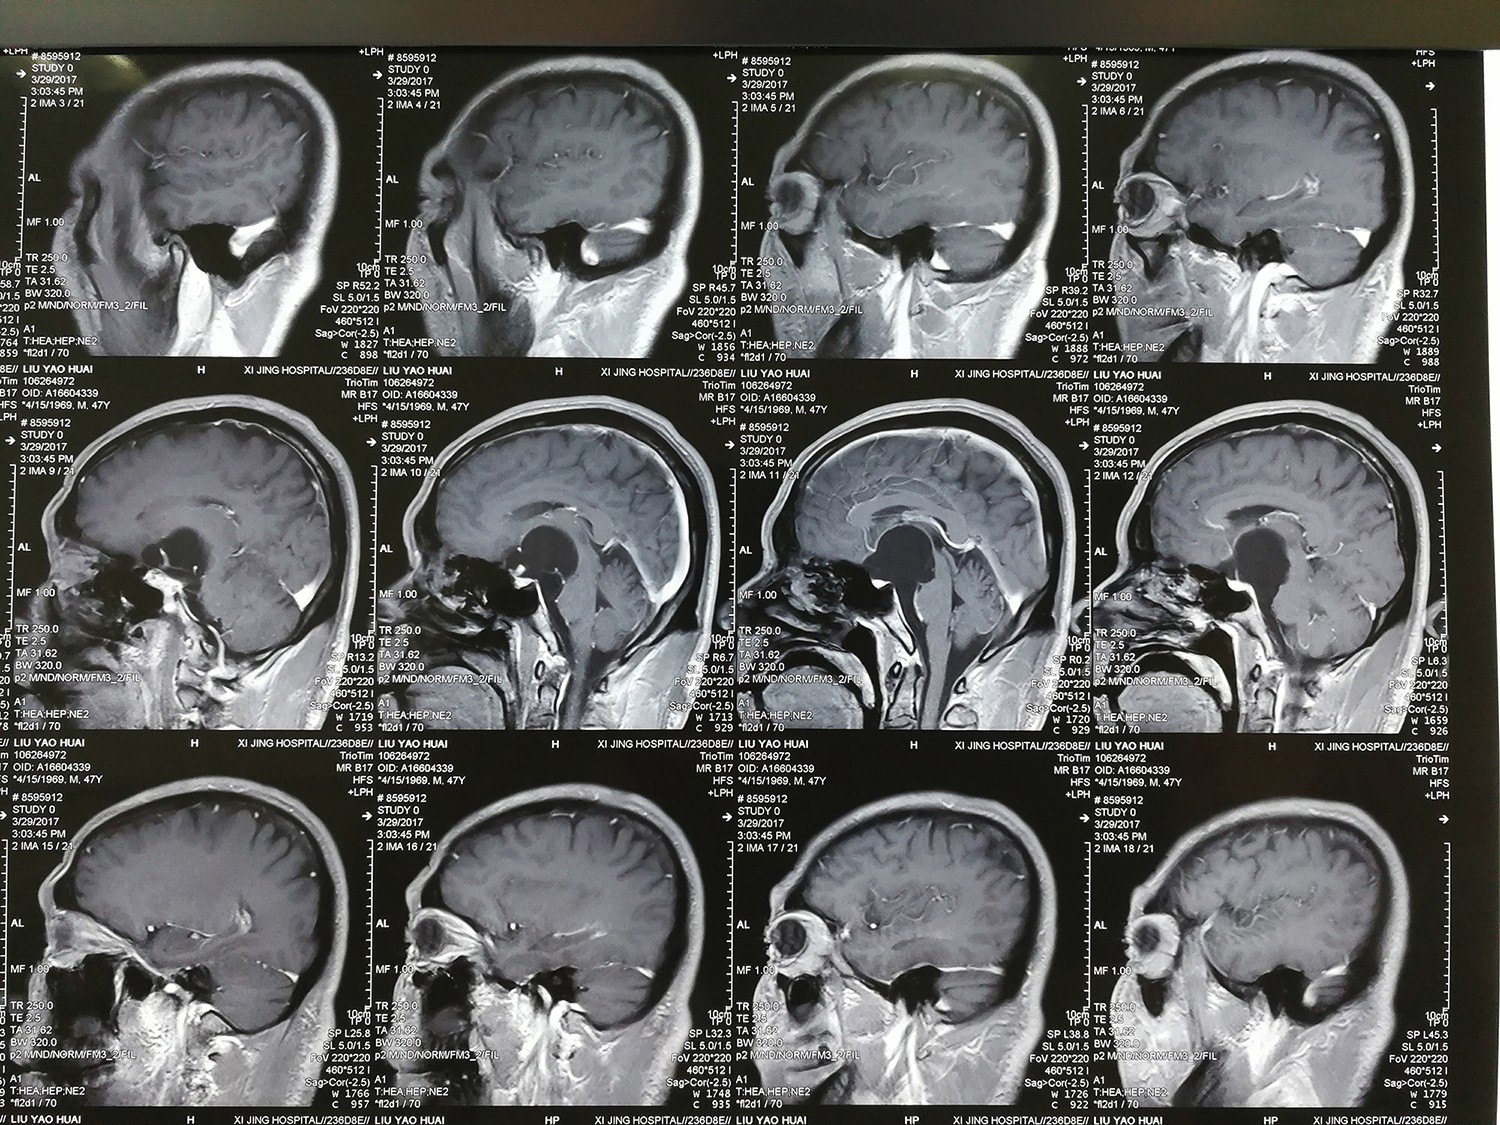

西京医院鞍区囊肿的手术治疗(实例)

图片尺寸766x566

刘心睿医师:应用脑室镜治疗鞍上池,桥前池囊肿合并梗阻性脑积水一例